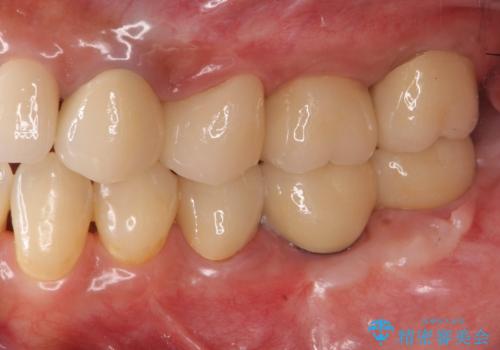

安定する噛み合わせの位置を探りながらの治療となりました。

最終的に非常に安定した咬合関係を構築できたので、しっかりとどんな食事でも楽しめると同時に、清掃性も高く清潔な口腔内環境を確立できました。